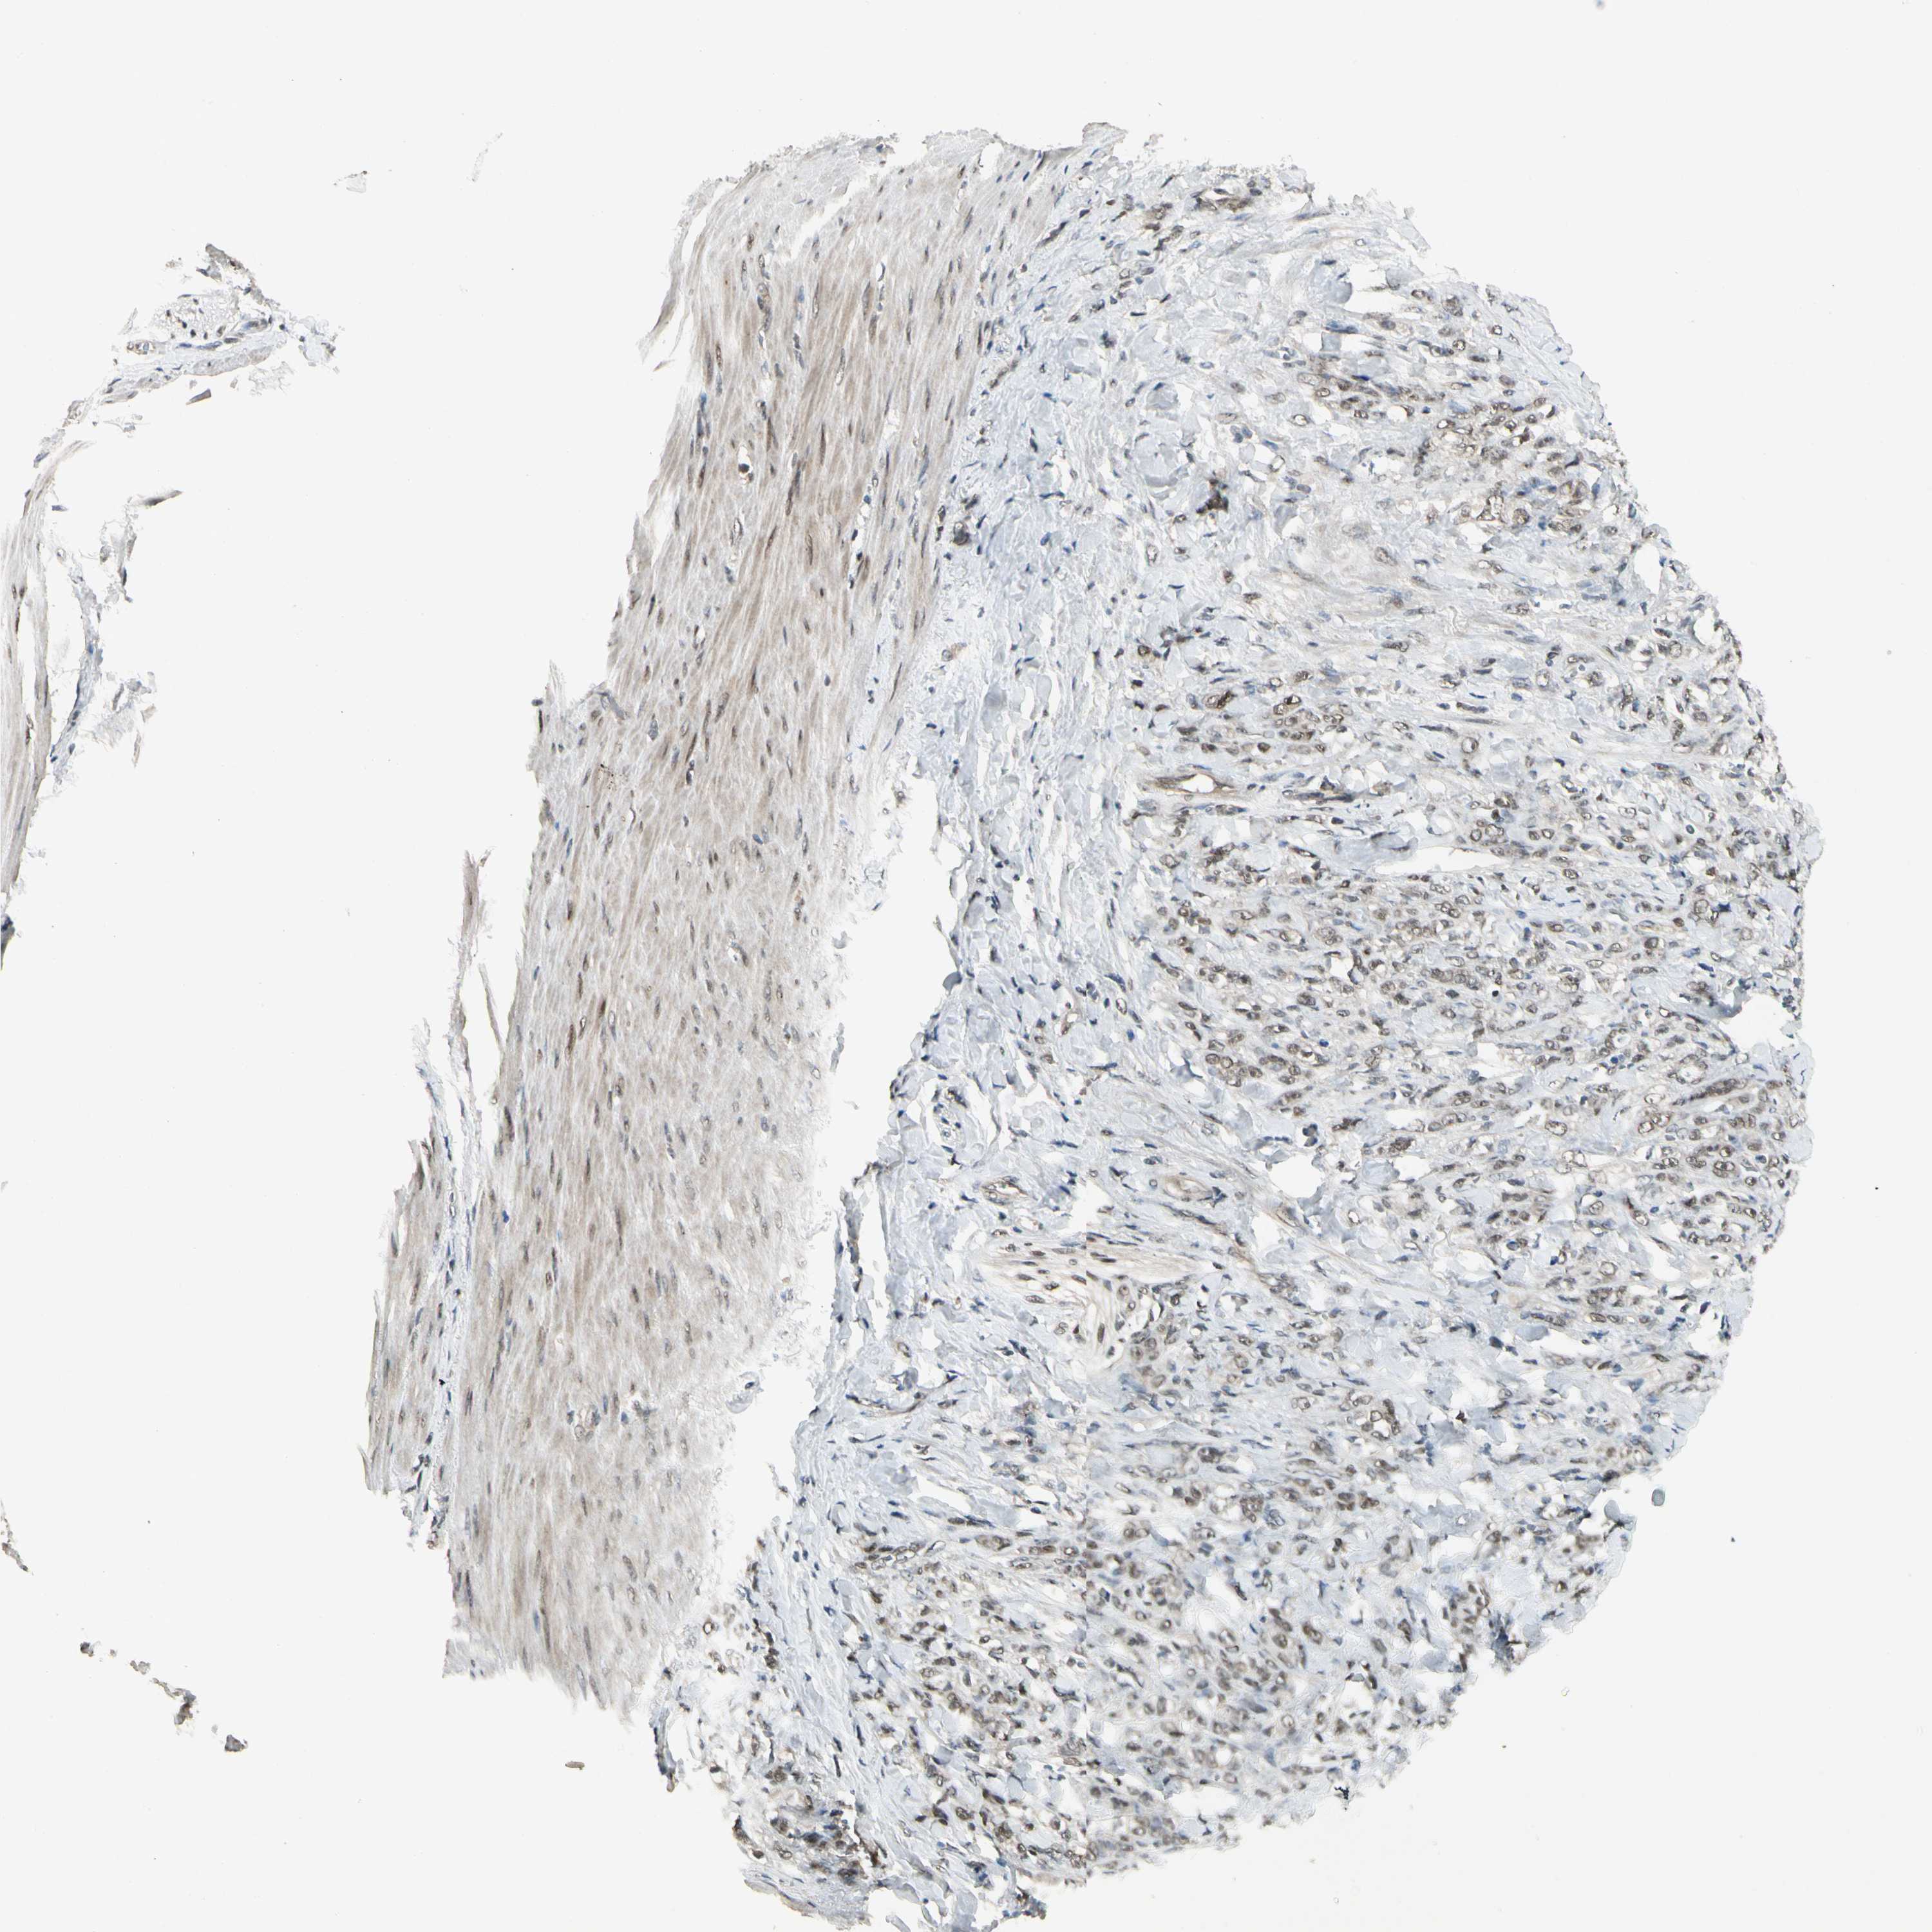

STOMACH CANCER - Protein expressioni

A mouse-over function shows sample information and annotation data. Click on an image to view it in a full screen mode. Samples can be filtered based on level of antibody staining by selecting one or several of the following categories: high, medium, low and not detected. The assay and annotation is described here.

Note that samples used for immunohistochemistry by the Human Protein Atlas do not correspond to samples in the TCGA dataset.

Antibody stainingi

Antibody staining in the annotated cell types in the current human tissue is reported as not detected, low, medium, or high, based on conventional immunohistochemistry profiling in selected tissues. This score is based on the combination of the staining intensity and fraction of stained cells.

Each image is clickable and will lead to virtual microscopy that enables deeper exploration of all samples and also displays staining intensity scores, fraction scores and subcellular localization as well as patient and tissue information for each sample.

Antibody HPA007990

Staining

High

Medium

Low

Not detected

Intensity

Strong

Moderate

Weak

Negative

Quantity

>75%

75%-25%

<25%

None

Location

Nuclear

Cytoplasmic/membranous

Cytoplasmic/membranous,nuclear

Adenocarcinoma, NOS